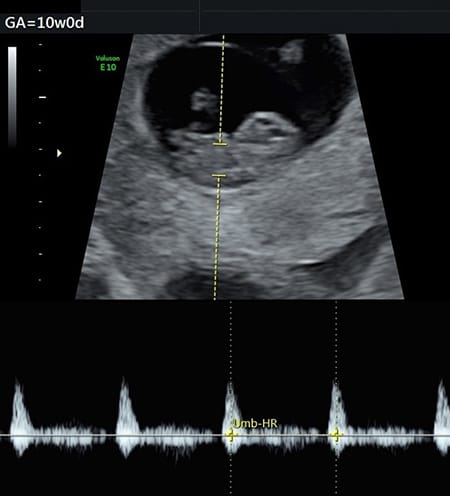

妊娠10週 胎児の様子は 母体の状態は おむつのムーニー 公式 ユニ チャーム